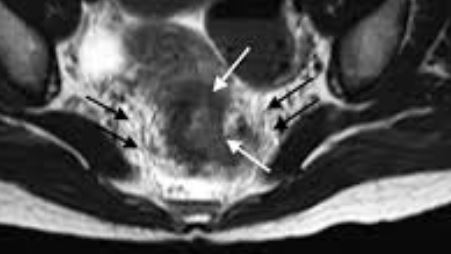

항문피를 경험하면 대개 치질이 아닐까 걱정하는데, 사실 걱정해야 할 것은 치질보다는 실제 건강에 큰 위험을 주는 대장암을 걱정해야 합니다.

물론 치질이 항문 출혈의 가장 흔한 질병인 것은 맞지만, 치열이나 혹은 대장암 등을 의심해야 하는 것이 좋습니다. 대장암의 하나의 증상이 바로 항문피이기 때문입니다.